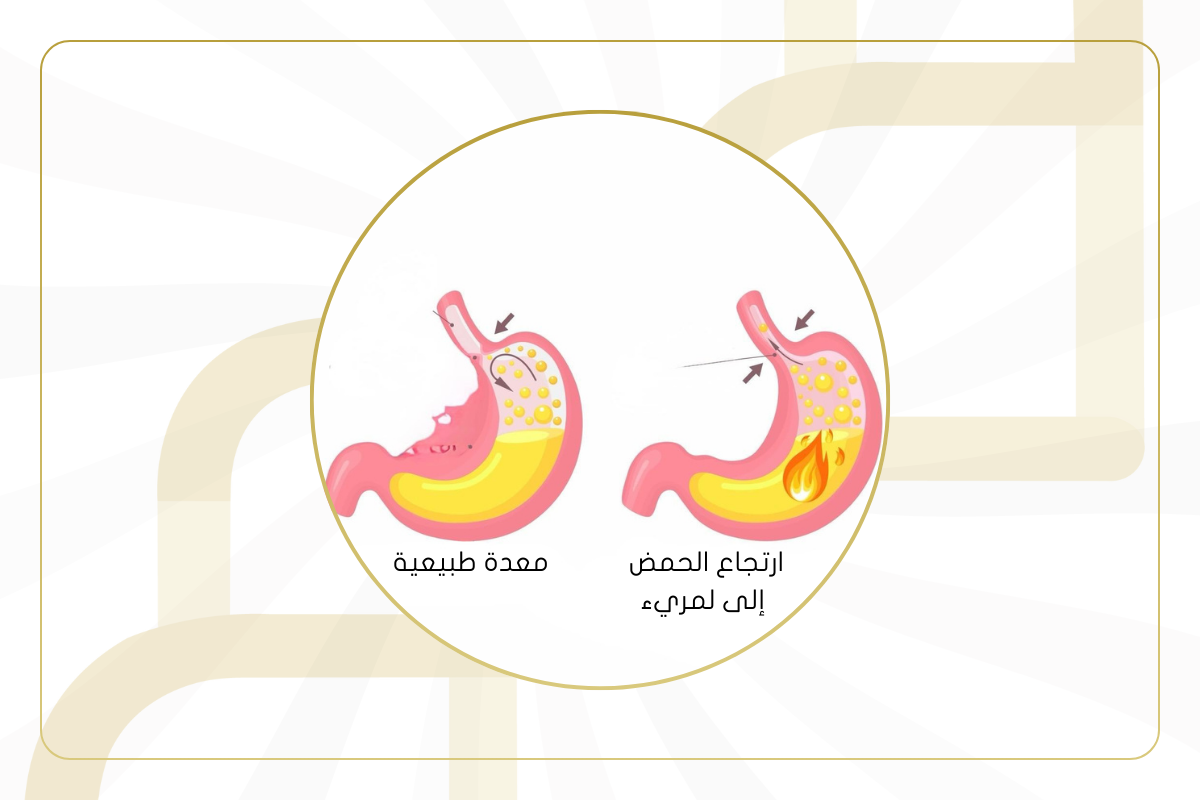

لا يوجد "شكل" محدد لارتجاع المريء يمكن رؤيته من الخارج، ولكنه يسبب تغيرات داخ...